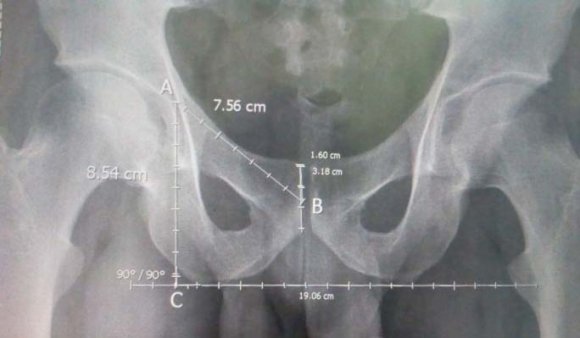

The measurement were carried out with the measuring tools available on the software of the system. All the measurements were carried out with appropriate magnification. The parameters measured were pubic length and ischial length.Pubic length is a straight line drawn on the radiograph from centre of the triradiate cartilage to the medial end of pubic symphysis.Ischial length is a straight line drawn on the radiograph from triradiate cartilage perpendicular to the line joining the bilateral lower ischial tuberosities (Figure 1). All the measurement were taken twice and the average recorded as the actual distance to ensure accuracy. Ischiopubic index is determined from pubic length divided by ischial length and then multiplied by 100.